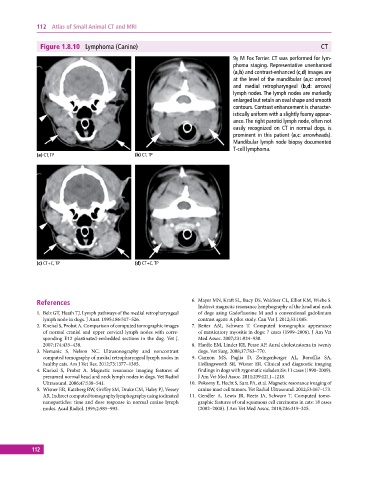

Figure 1.8.10 Lymphoma (Canine) CT

9y M Fox Terrier. CT was performed for lym-

phoma staging. Representative unenhanced

(a,b) and contrast‐enhanced (c,d) images are

at the level of the mandibular (a,c: arrows)

and medial retropharyngeal (b,d: arrows)

lymph nodes. The lymph nodes are markedly

enlarged but retain an oval shape and smooth

contours. Contrast enhancement is character-

istically uniform with a slightly foamy appear-

ance. The right parotid lymph node, often not

easily recognized on CT in normal dogs, is

prominent in this patient (a,c: arrowheads).

Mandibular lymph node biopsy documented

T‐cell lymphoma.

(a) CT, TP (b) CT, TP

(c) CT+C, TP (d) CT+C, TP